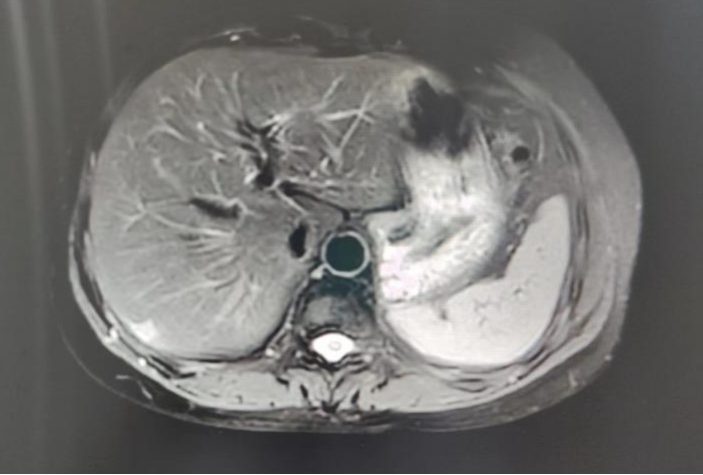

上腹部MR平扫+增强:肝右叶包膜下结节,考虑转移可能。